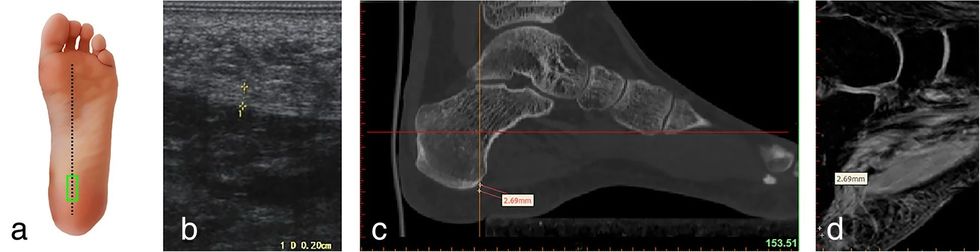

Një radiografi ose një skanim MRI mund të jetë e nevojshme për të kontrolluar që asgjë tjetër nuk po ju shkakton dhimbje në thembra, siç është fraktura e kockave.

Mjeku juaj mund të përdorë një pajisje me ultratinguj për të ndihmuar në përcaktimin e vendit më të mirë për injeksion. Ata gjithashtu mund të aplikojnë kortikosteroide në lëkurën e thembrës tuaj ose harkut të këmbës tuaj, dhe më pas të aplikojnë një rrymë elektrike pa dhimbje për të lënë steroidin të kalojë nëpër lëkurën tuaj dhe në muskul.

Steroidet mund të injektohen përmes qasjeve plantare ose mediale me ose pa udhëzime me ultratinguj. Studimet kanë gjetur që trajtimet me steroide kanë një normë suksesi prej 70 për qind ose më të mirë.